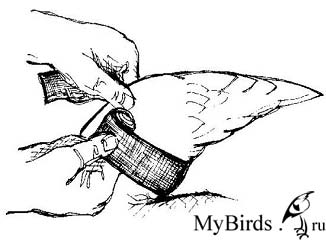

Консервативная фиксация с помощью крестообразной повязки. Photo: C. Haupt

Консервативная фиксация должна проводиться только на одной стороне, и используемый для повязки материал не должен повредить перья. Наиболее подходящими являются самоклеящиеся повязки. Неповрежденное оперение для птицы столь же жизненно важно, как и целостный скелет. Свою эффективность доказала крестообразная повязка (см. рисунки). После удаления повязки птицу необходимо несколько дней тренировать, чтобы укрепить ее мышцы. С этой целью ее можно заставлять каждый день карабкаться вверх с одновременным взмахиванием крыльев или поощрять ее упражняться на полу. Не рекомендуется разрешать птице летать в помещении, т.к. стрижи развивают высокую скорость за короткое расстояние, и птица может легко причинить себе вред.

Крыло расположено в физиологическом положении. Чувствительную к давлению растянутую кожу крыла (показано стрелкой) необходимо осторожно удерживать в пальцах. Рисунок: C. Haupt

Эластичная повязка накладывается снизу вверх вокруг плечевой кости, затем через плечевой сустав и вокруг запястья. Рисунок: C. Haupt

Повязка располагается дорсально через крыло, снова перетягивается крестообразно снизу и вдоль под плечевой костью. Рисунок: C. Haupt